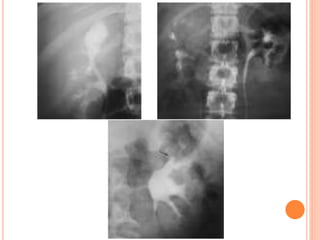

PREVOIDING IMAGING

If reflux is observed during late bladder

filling, the ipsilateral renal fossa may be

imaged in the anteroposterior projection

prior to voiding.

POSTVOIDING IMAGING

At the conclusion of voiding, each

renal fossa should be imaged. Still

images may demonstrate reflux that is

not appreciated at fluoroscopy as well

as other anomalies or abnormalities.

INTERMEDIATE FILLING

Vesicoureteral reflux can be

seen on oblique radiographs

obtained just before voiding

and can be graded after

voiding with the International

Reflux System.

VCUG is commonlyperformed in children with prenatally diagnosed hydronephrosis, urinary tract infections, and voiding abnormalities. The procedure should include assessment of the spine and pelvis; masses or opaque calculi; bladder capacity, contour, and emptying capability; presence and grade of reflux; and urethral appearance.

PREVOIDING IMAGING If refluxis observed during late bladder filling, the ipsilateral renal fossa may be imaged in the anteroposterior projection prior to voiding.

POSTVOIDING IMAGING At theconclusion of voiding, each renal fossa should be imaged. Still images may demonstrate reflux that is not appreciated at fluoroscopy as well as other anomalies or abnormalities.